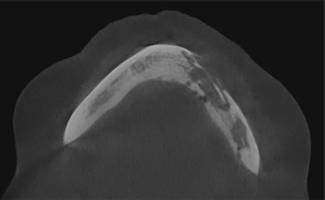

Osteomyelitis bedeutet „Knochenmarkentzündung“. Diese kann auch im Kiefer auftreten. Ursache kann z.B. eine „verschleppte“, lang andauernde bakterielle Knocheninfektion nach Entzündung um eine Zahnwurzel sein. Häufig kann die Ursache jedoch auch nicht mehr genau geklärt werden. Die Patienten klagen über leichte bis mittelstarke Schmerzen, Kribbelgefühle und / oder andere Missempfindungen im Kiefer, deren genaue Ausdehnung sich manchmal nur vage bestimmen lässt. Bei der Untersuchung findet sich als indirektes Zeichen häufig eine gerötete, druckschmerzhafte Schwellung am Kiefer als Zeichen der begleitenden Entzündung des umgebenden Weichgewebes. Wenn nur der Knochen betroffen ist, kann die Untersuchung auch völlig normal sein. Als Bildgebung kommen, angepasst an den jeweiligen Fall, Röntgenbilder, DVT (Digitales Volumentomogramm), CT, MRT und eine Szintigraphie in Frage. Hierdurch soll herausgefunden werden, ob und in welchem Ausmaß das Knochenmark entzündet ist.

Bei der Osteomyelitis ist eine genaue Untersuchung und sorgfältige Behandlung besonders wichtig, weil dieses Krankheitsbild noch nicht in allen Details verstanden ist und nur bei prompter und adäquater Behandlung die Chancen besteht, eine langwierige Erkrankung zu vermeiden.

Therapeutisch bietet das Universitätsklinikum Düsseldorf die nur an wenigen Standorten in Deutschland verfügbare Möglichkeit, mittels „hyperbarer Sauerstofftherapie“ (HBO=“ hyperbaric oxygen therapy“) den erkrankten Knochen zu behandeln. Durch die optimale Sauerstoffversorgung wird die Chance zur Aufteilung der Entzündung verbessert. Unterstützt wird diese Behandlung durch Antibiotikagabe zur Bekämpfung der krankheitserregenden Bakterien vor Ort. Wenn chirurgische Maßnahmen nicht zu vermeiden sind, müssen gegebenenfalls die entzündeten Knochenabschnitte angefräst (Dekortikation) oder entfernt werden. Resezierte Kieferabschnitte werden in derselben Operation oder später durch Knochentransplantate ersetzt.